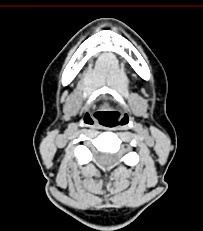

Оптимальным методом обследования гортани и голосовых связок является мультиспиральная компьютерная томография. Метод позволяет подробно визуализировать состояние данной анатомической области и выявить патологические изменения, которые незаметны при ларингоскопии (визуальный осмотр гортани с помощью специальных инструментов), проведении УЗИ и обычной рентгенографии.

Компьютерная томография особенно полезна для оценки состояния хрящей гортани, которые лучше всего визуализируются с помощью данного исследования. В частности, мультиспиральная КТ позволяет выявить распространение рака гортани в ткань щитовидного хряща и другие окружающие структуры.

На полученных снимках можно оценить состояние всех структурных элементов гортани, голосовых складок, хрящей, а также лимфатических узлов, сосудов и шейных позвонков на исследуемом уровне. Инновационные возможности аппарата позволяют построить 3D-модель зоны исследования, которая дает наглядную картину пространственного расположения органов, что бывает особенно важно при планировании хирургических операций.